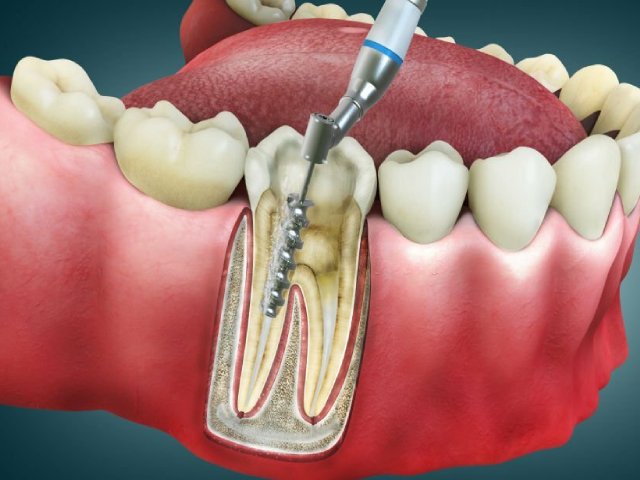

Whether it’s routine dental care, cosmetic procedures, or complex treatments like Root Canal Therapy or OSMF management, Dr. Rathore ensures every patient receives personalized attention and quality care.